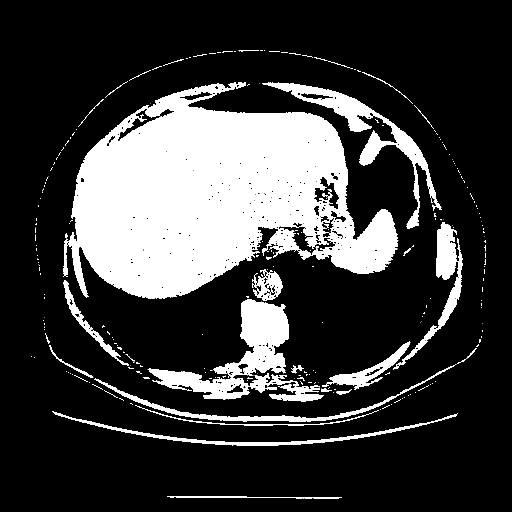

Image Grid

4Γ—3 grid: Rows show different image types (Original NATIVE, Reconstructed NATIVE, Original VENOUS, Generated VENOUS), Columns show windowing techniques (No Window, Lung Window, Mediastinum Window)

Original NATIVE CT scan (input)

Full window (WL 1023.5, WW 4095 β†’ Low βˆ’1024, High +3071)

Actual HU range: [-1024.0, 3071.0]

Original VENOUS CT scan

Generated VENOUS CT scan (A→B translation)